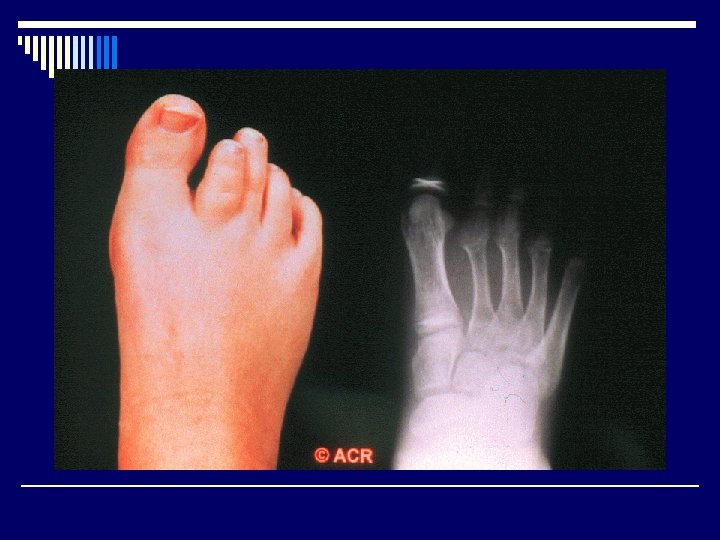

o Localized inflammation and cytokine release o Increase blood flow -macroepiphysis o Longer affected leg

Radiological features o Joint effusion o Erosion o Joint space narrowing o Joint deformity o Osteoporosis o Bony ankylosis